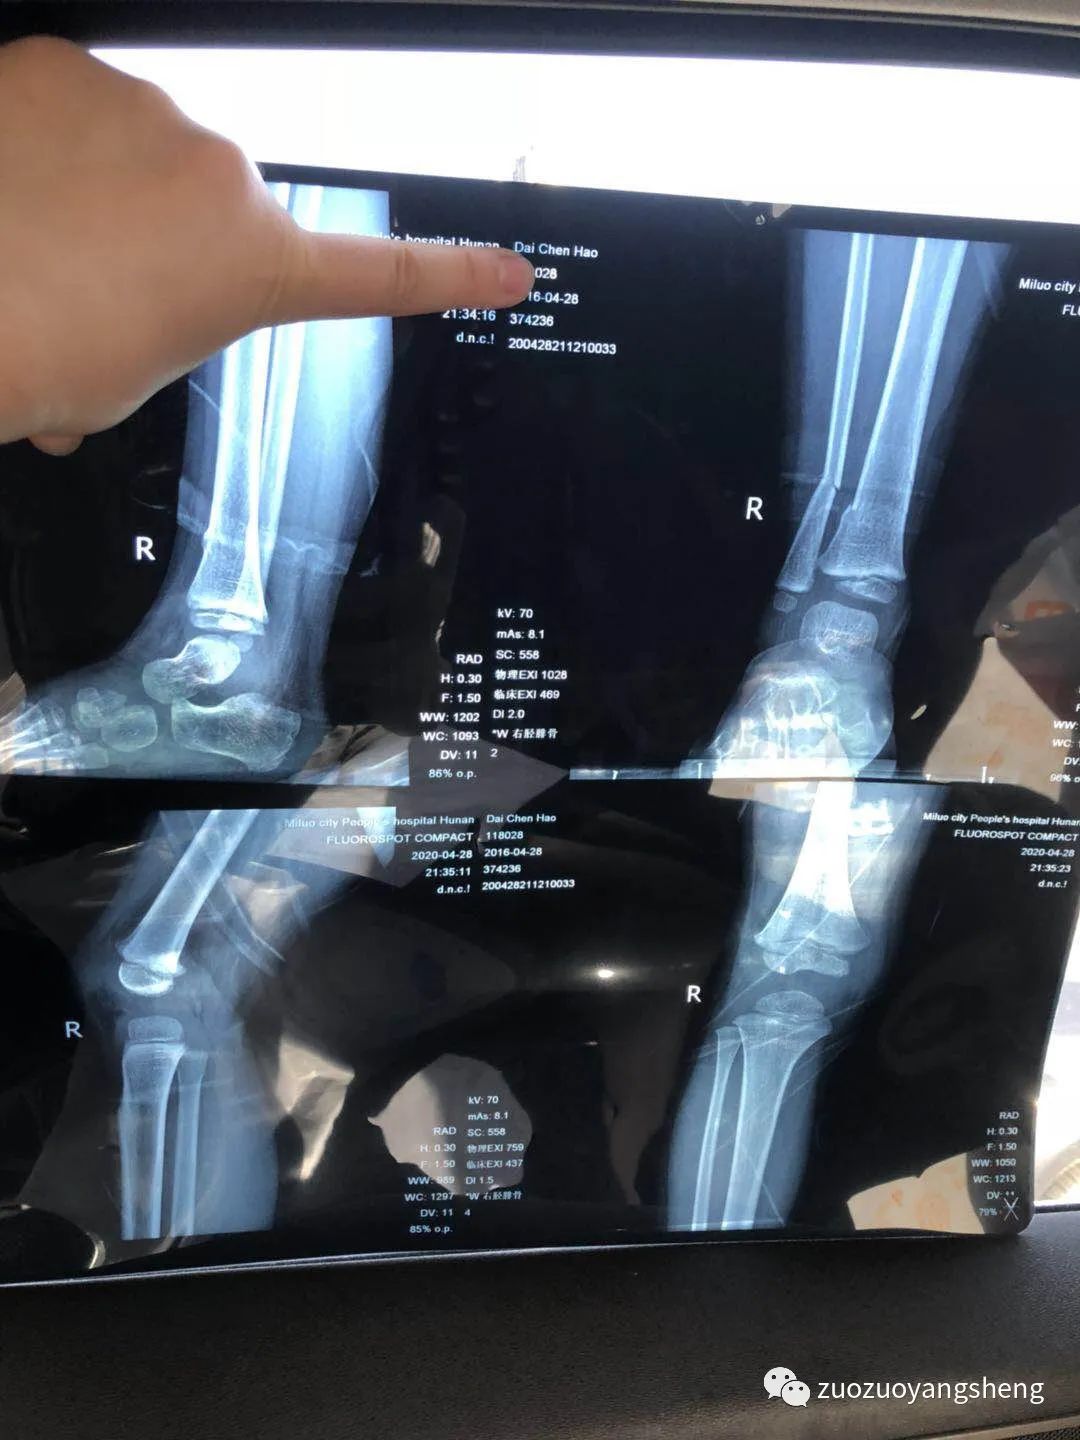

也许是感受到了我的变化,拍片子的时候他真的很乖。只是意外并不因为他的懂事而对他网开一面,结果显示右胫腓骨下端骨折、挨着的胫骨处有细微裂痕。

附骨折第一天检测单据:

附骨折第一周复查单据:

附检测单据:

孩子因为拆了石膏,安全感全失,吵闹了两天腿疼。同学说这个是正常现象,看了拍照发给他的片子后说,骨裂还是这么多要注意一下就好。